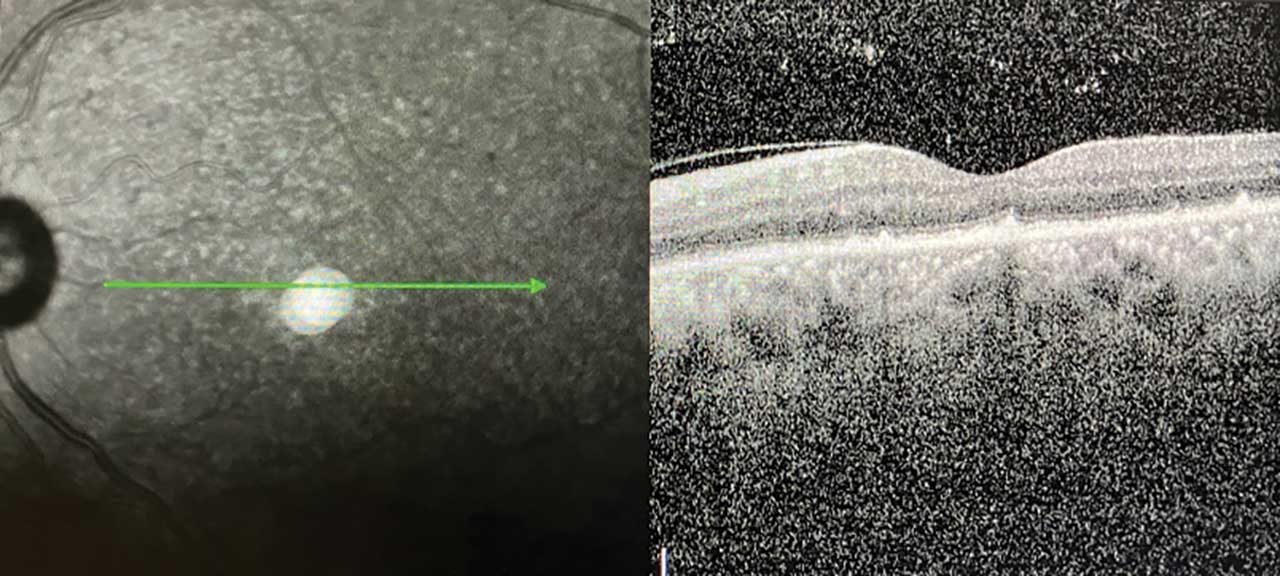

Imaging modalities helpful in the diagnosis and monitoring of ocular syphilis in the retina, choroid, and vitreous include optical coherence tomography (OCT), autofluorescence, fundus photographs, and fluorescein angiography. Lesions typical of syphilis that are present in the retina of patients with syphilitic uveitis include placoid lesions, pyramidal deposits, loss of ellipsoid zone, and vitreous cells (Figure 3).

Optical coherence tomography findings include pyramidal deposits of subretinal fibrosis, subretinal fluid, and loss of the ellipsoid zone.11 Fluorescein angiography will show hypofluorescence in the areas of placoid lesions as early blocking with late pooling and staining in a segmental distribution.11